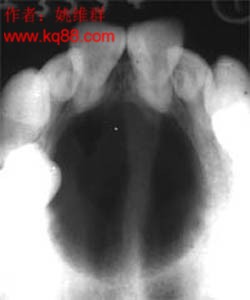

4.X線攝片示頜骨膨隆,不規則多房性囊性透光影像,此影像邊緣不光滑,有半月狀切跡,分房大小懸殊,波及牙槽骨者可有明顯的“根尖浸潤征”--牙根尖的牙槽突骨質呈不規則的破壞與吸收,牙根可呈鋸齒狀或截斷樣吸收。